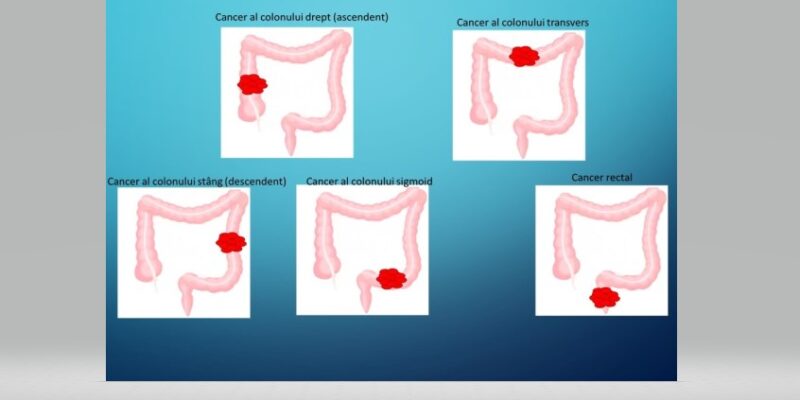

TRATAMENTUL CHIRURGICAL ÎN CANCERUL COLORECTAL REZECABIL, ÎN FUNCȚIE DE LOCALIZAREA TUMORII

Primul pas în stabilirea tratamentului unui pacient cu cancer colorectal îl reprezintă sosirea rezultatului histopatologic al pieselor de biopsie, care confirmă diagnosticul. Ulterior se stabilește extensia cancerului, atât cea loco-regională cât și la distanță. În cazul în care tumora este...